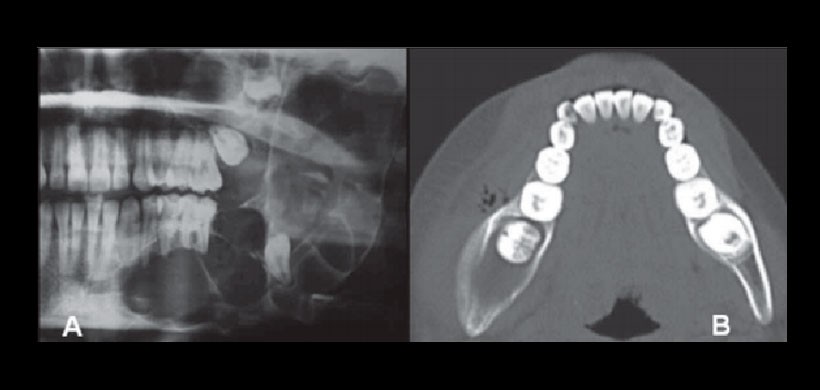

Figura 1: (A) Radiografía panorámica de un TOQ que se presenta como una gran radiolucidez multilocular con desplazamiento de piezas dentales y afección de maxilar inferior. Fuente: Srivatsan 2014. (B) Corte axial de un CBCT que muestra la extensión de la lesión producida por un TOQ. (Fuente: Alatorre 2014)